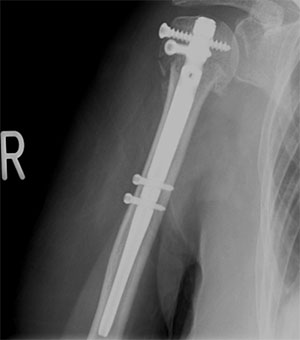

骨折後の手術例

上腕骨頚部骨折